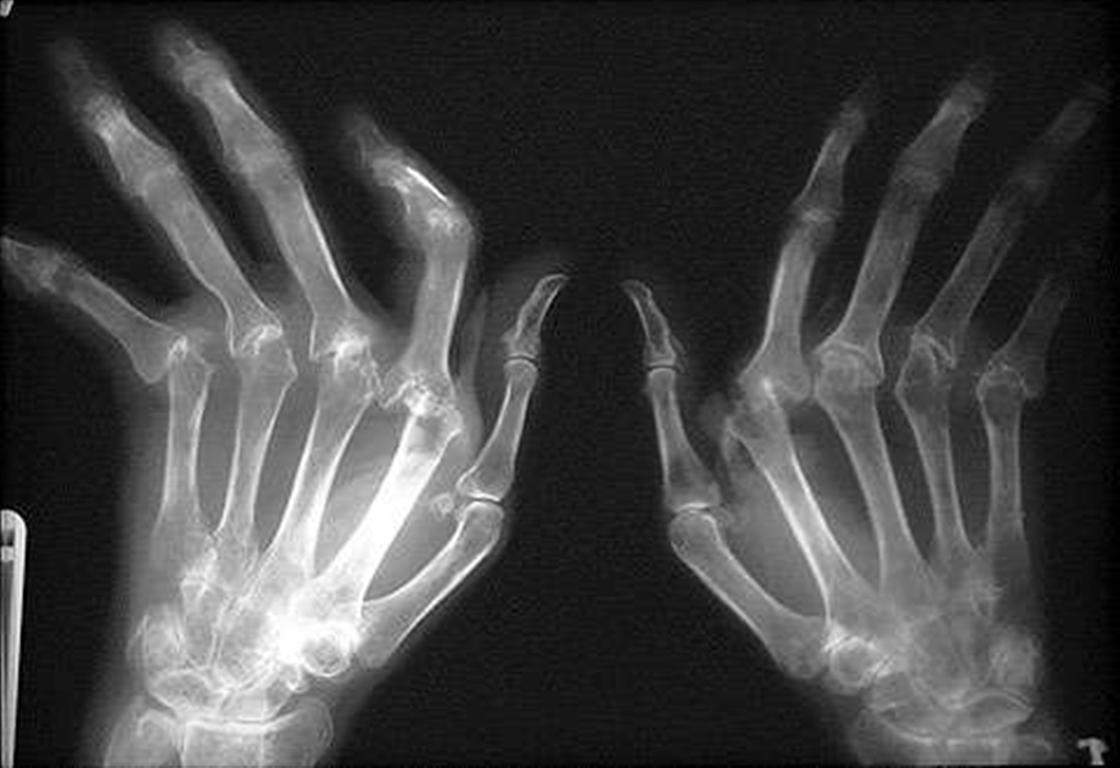

Ниже представлены фотографии, иллюстрирующие различные стадии и симптомы полиартрита пальцев рук:

Фото 3: Ограничение движения пальцев, искривление и скручивание суставов.